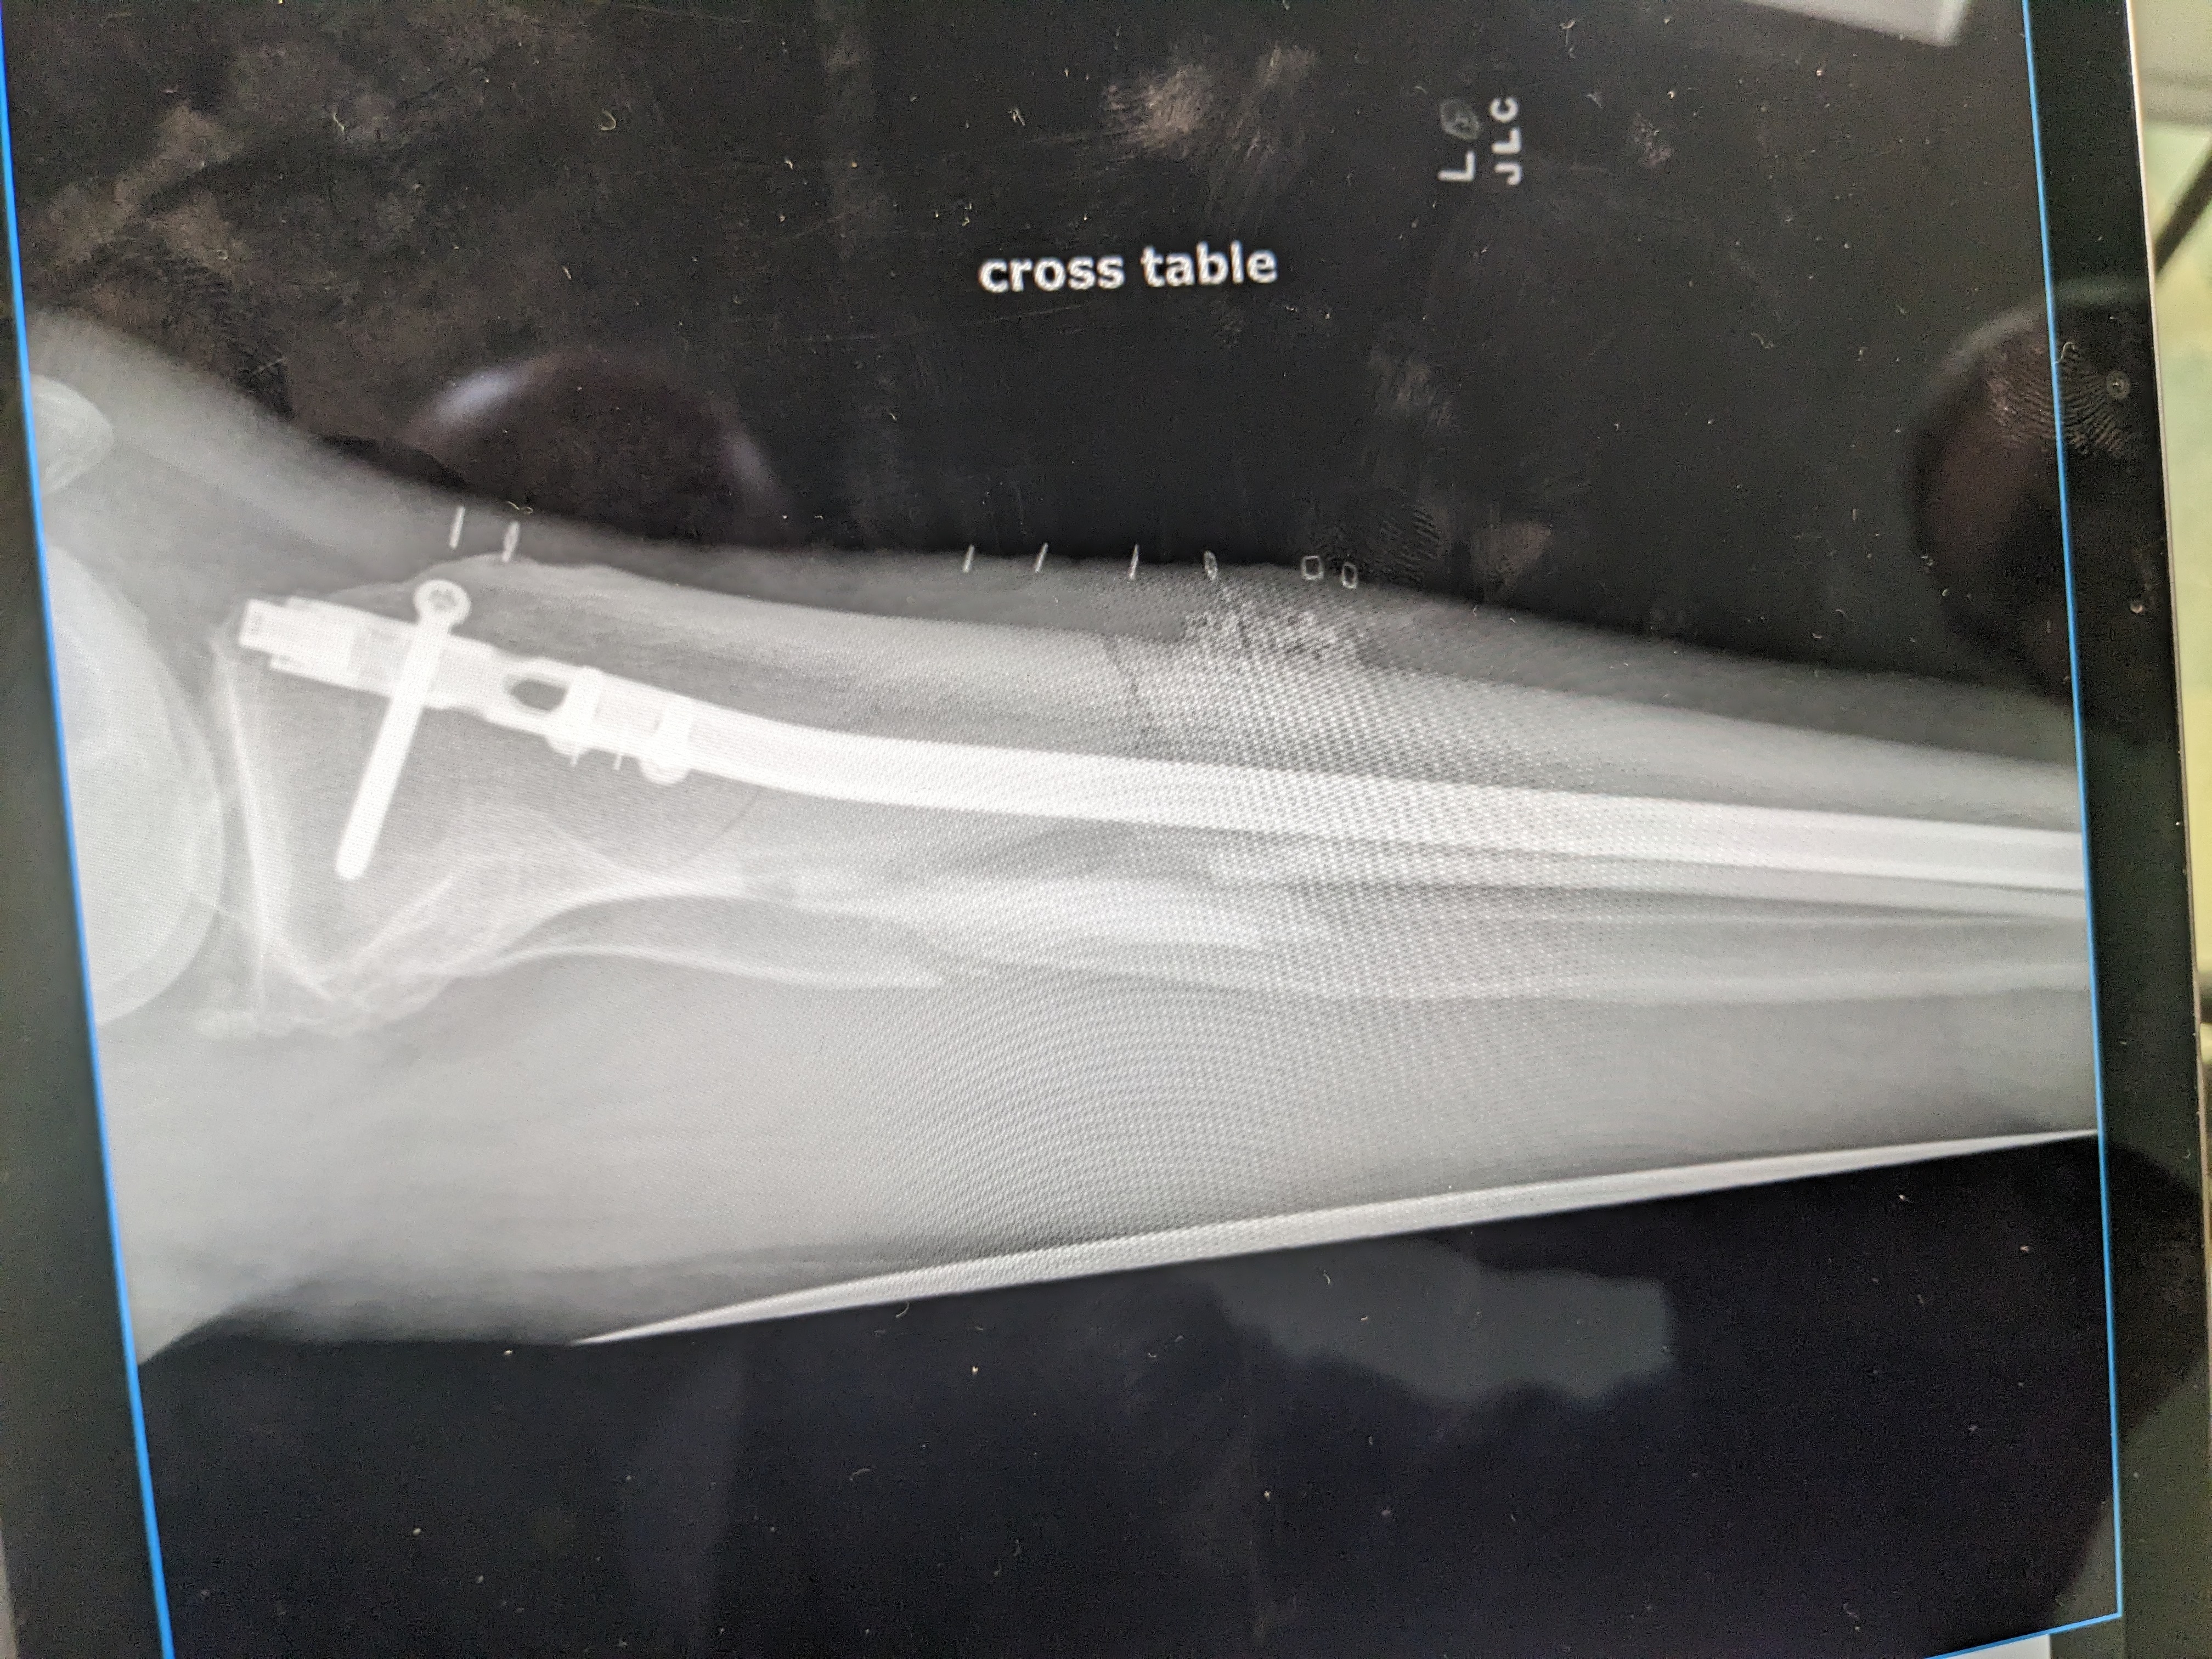

Calf was crushed. Multiple compound fractures bone piercing the bloody flesh.

My platoon of guardian angels prevented my knee and ankle from being destroyed, thus the surgical team was able to install at least a 1/2 pound of titanium to reconstruct what was left of my calf, as there was enough bone left to attach the titanium bones to the joints. I have nerve damage.

I underwent a third operation on my poorly healing bones. Hopefully this much hardware will allow what bones remaining to fuse. My leg is now more stable but traumatized after being opened up again.

Wow. Looks like an Ace Hardware store.

Wow that is a lot of hardware in a small space. Sure hope your recovery continues well and you can get back on your tractor.

New hardware is providing more stability. Now only hope the crunched Tibia begins to mend.